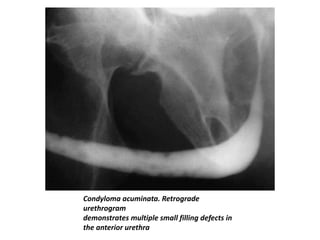

Condyloma Acuminata

• Condyloma acuminata are caused by viral infection and

produce soft, sessile, squamous papillomas on the

penile glans and shaft and the prepuce.

• Urethral involvement occurs in 0.5%–5% of male

patients.

• The use of catheterization, instrumentation, and

retrograde urethrography is not recommended

because of the possibility of retrograde seeding.

• The diagnostic procedure of choice is voiding

cystourethrography.

• The typical urethrographic findings are multiple

papillary filling defects in the anterior urethra.

Condyloma acuminata. Retrograde

urethrogram

demonstrates multiple small filling defects in

the anterior urethra